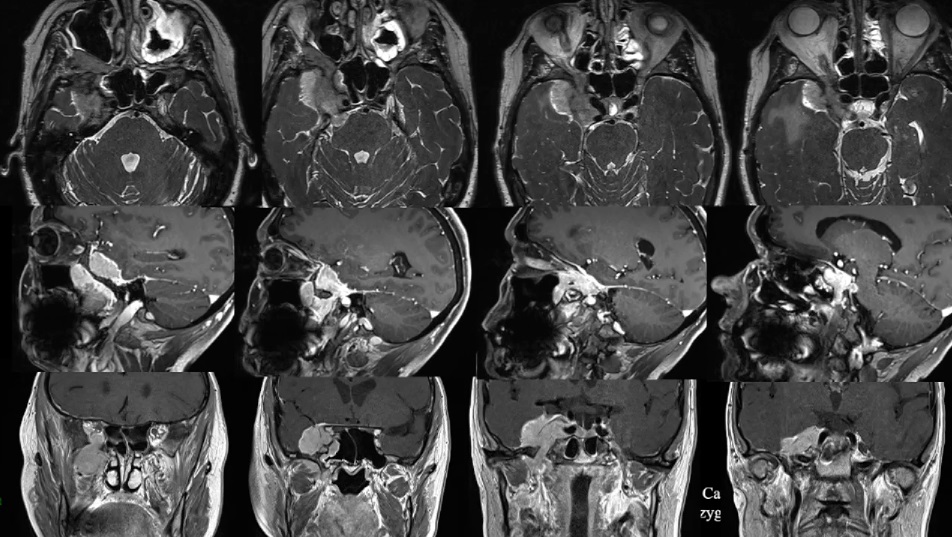

53岁男性高难度岩斜区脑膜瘤

53岁男性累及海绵窦和Meckel's腔的脑膜瘤

75岁女性-视神经管脑膜瘤,肿瘤切除与好转视力如何兼得?

52岁女性-较大蝶窦-海绵窦脑膜瘤,如何才能顺利手术?